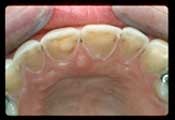

• Bulimia. Bulimia nervosa is a serious eating disorder that is characterized by self-induced vomiting as a means to maintain a desired weight.4, 7, 33 It is a relatively common disorder among women in Western industrialized nations, with a prevalence of approximately 5% in 18-35 year-old females.7 Among individuals with bulimia, the prevalence of erosion has been reported to be over 90%.7 Individuals with bulimia or other eating disorders are commonly found to have poor oral health, with one systematic review finding that patients with eating disorders and/or self-induced vomiting had five to seven times higher risk of dental erosion.34 Because patients with bulimia are generally of average weight, dentists are often the first to recognize the condition by the characteristic erosion of the lingual-palatal aspect of the anterior maxillary teeth (i.e., perimolysis or perimylolysis, see photos below),4, 7 caused by the forceful expulsion of stomach acids onto the front teeth during vomiting. These patients should be cautioned against brushing their teeth immediately after vomiting.  One study found that 80 % of participants with eating disorders had extensive erosion when brushing after vomiting. After vomiting, patients should rinse with water, a sodium bicarbonate rinse, or milk.4

Figures, below. Characteristic erosion pattern from bulimia.

Exterior view of enamel erosion of the lingual-palatal aspect of the anterior maxillary teeth (i.e., perimolysis or perimylolysis)Internal view of enamel erosion of the lingual-palatal aspect of the anterior maxillary teeth (i.e., perimolysis or perimylolysis)

Photos courtesy of Craig Mabrito, D.D.S.